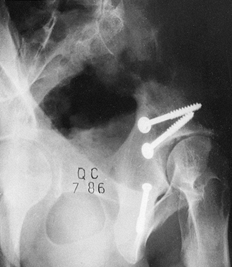

![]() |

Figure 11.24. A grade 3 open tibial fracture with bone loss in a patient with other open fractures. A: Clinical appearance on admission. B: Radiographic appearance on admission. C,D:

Stabilization of the fracture with two-plane bilateral pin configuration proximally and three anterior pins distally. Bone graft had been delayed for 3 months because of adult respiratory distress syndrome. E: At 8 months, after the patient had started full weight bearing, the frame was gradually reduced. As a last step before removal, the proximal pin was loosened. F: Radiographs 1 year after injury. |